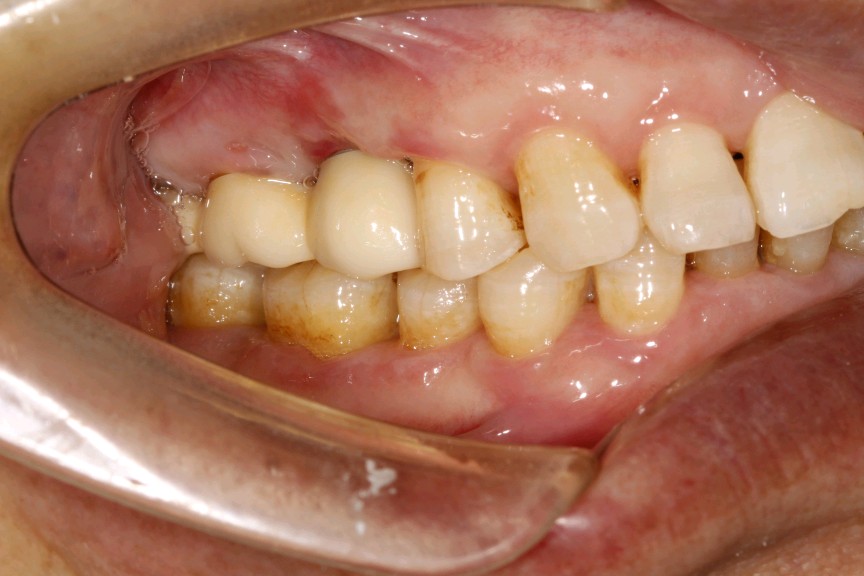

口内的牙齿息息相关,缺少任何一颗都会影响口腔功能的完整性,后牙长期缺失,咀嚼功能会逐渐退化,导致咀嚼不便。一侧后牙缺失,会习惯性的偏侧咀嚼,从而也会影响颞下颌关节的功能。颞下颌关节是联动的关节,左侧关节运动,右侧关节自然而然也要运动。所以他要求两侧关节受力都比较均匀才会对关节有好处。长期偏侧咀嚼还会导致关节受挫,引发关节性疾病。

缺牙时间越长,对余留牙齿的影响将会越大。牙齿是陪伴我们一生的重要伙伴,口腔健康与身体健康密切相关,所以缺牙的朋友们,一定要尽早修复,及时止损